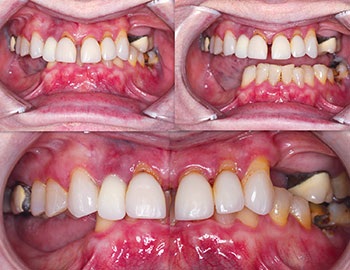

Our patient, a healthy woman in her early 60s, presented with a terminal dentition (Fig. 1) in both arches, collapsed bite, unstable occlusion, midline shift, asymmetric horizontal plane and bone loss (Fig. 2). She was looking for a fixed solution that would give her the confidence to smile, eat and socialize without restrictions. Several previous treatment plans suggested placing provisional dentures as an interim until the implant stabilized, which did not resonate with her desires during the healing phase.

The patient wore the updated temporaries for an additional three-month healing period to ensure complete osseointegration and stability. At follow-up visits, she reported no discomfort, stable occlusion and improved confidence in function. However, just before final impressions, the patient expressed a change in her vision for her restoration:

This pivot required rethinking the original FP1 (full-arch hybrid) design, at least in the maxilla, and changing to a FP3 design.

After thorough evaluation, we planned for a FP3 restoration in the maxilla and mandible (implant-supported crowns that mimic natural teeth and allow for flossing) and a fixed prosthesis with pink material to replace tissue contours.

Thanks to close collaboration with LA Dental Implant Lab, we were able to redesign and mill a custom titanium substructure to ensure passivity and a precise fit. We used zirconia thimble supra structure design and individual crowns to allow flossing through embrasures. This fabricated individual, highly aesthetic zirconia crowns, creating a natural-looking, functional and hygienic restoration (Figs. 13–14).

Final seating: Perfect fit, zero adjustments

Final delivery day could not have gone smoother. No adjustments were needed—a testament to precision planning and execution along with digital workflows. Patient satisfaction was beyond expectations—she could floss between her teeth, enjoy a natural smile and eat comfortably. The occlusion was balanced and aesthetics were on point, and the patient left with tears of joy (Figs. 15–17).